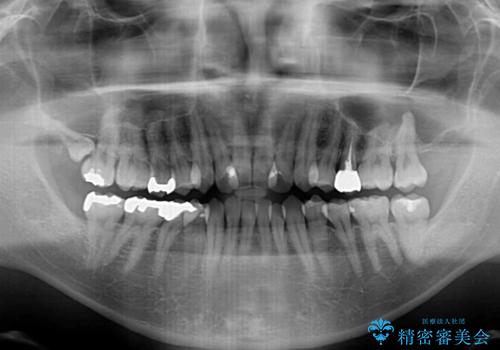

前歯のクロスバイト 目立たないワイヤー装置で矯正治療

- 前歯のクロスバイトを改善したいとのことで来院された患者様です。

マウスピース矯正では前歯の神経への負担が大きいことを懸念され、ワイヤー装置による矯正治療を行うこととしました。

舌の突出癖が認められたため、デコボコ改善に伴い前歯が前突する可能性があったため、舌のトレーニングをしっかりと行うよう指導しながら治療を進めることとしました。